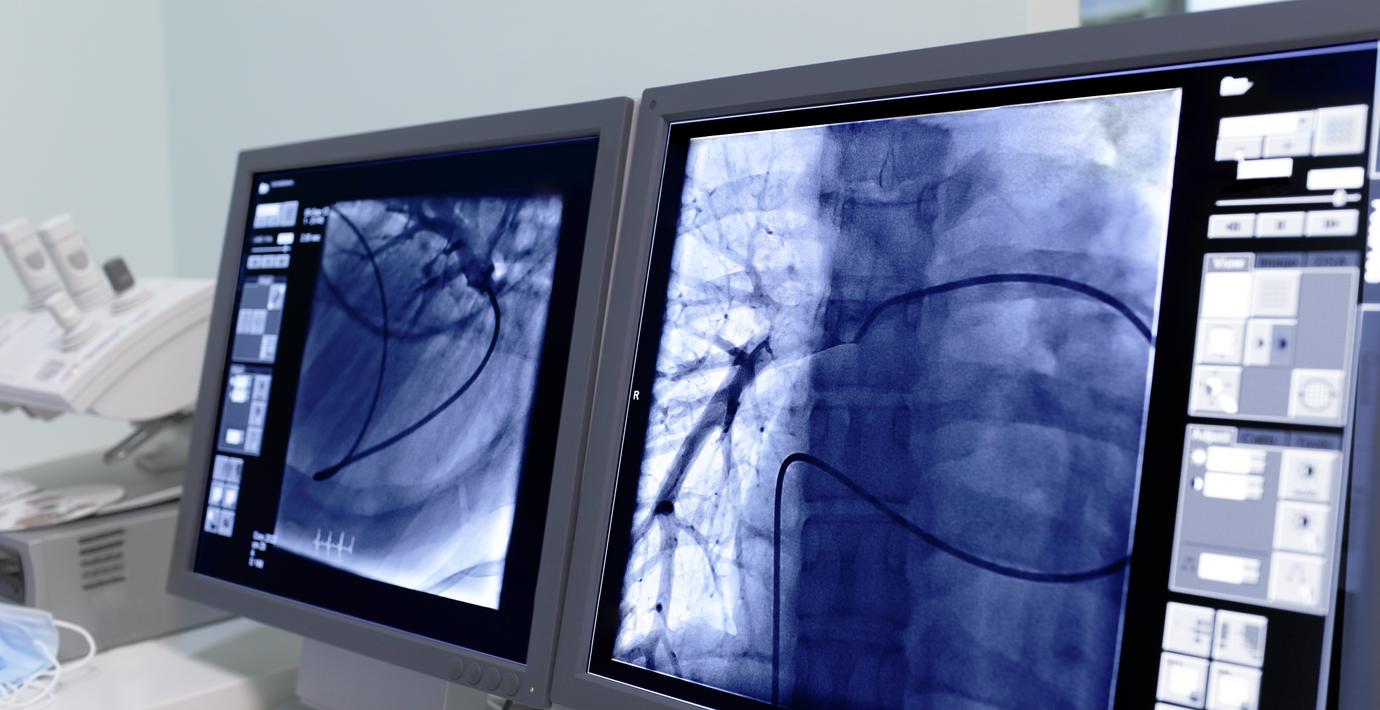

En 48-årig man i Norge upptäckte med hjälp av Chat GPT att en cysta i ryggen låg bakom hans svåra smärtor – något radiologerna på vårdföretaget Unilabs missat, rapporterar NRK. Mannen har anmält bolaget till den norska länsstyrelsen, som öppnat ett tillsynsärende.